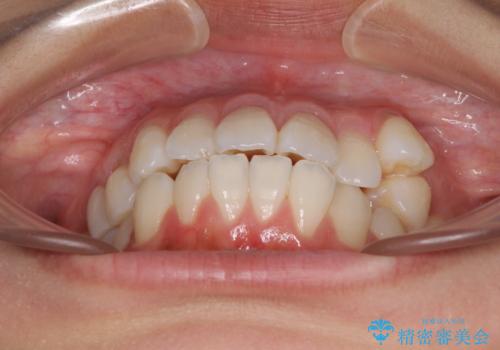

- 八重歯と口元の突出感を気にして来院された患者様です。

歯列が前方に突出しており、上下の正中がズレていたため、左側は上下第一小臼歯を、右側は上下第二小臼歯を抜去し、ワイヤー装置による矯正治療を行うこととしました。

当初はインビザラインによる矯正治療をご希望でしたが、正中を合わせたいことや、口元の突出感を改善したいことから、ワイヤー矯正を強く推奨しました。

治療期間は2年に満たず、スッキリとした口元に仕上がりました。